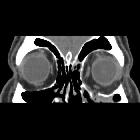

Medial blowout fracture

Medial blowout fractures are the second most common type, occurring through the lamina papyracea. Orbital fat and the medial rectus muscle may prolapse into the ethmoid air cells.

CT

CT is the modality of choice for assessment of the facial skeleton. A full assessment does not require the administration of contrast. Ideally, the acquisition should be performed using the thinnest detector settings, enabling thin-slice reconstructions along three orthogonal planes with a bone algorithm. Additional soft tissue algorithm reconstructions using larger slice thickness and 3D volumetric reconstruction are useful for assessing associated soft tissue injury and gauging facial asymmetry, respectively.

In addition to evaluating the location and extent of fracture(s), other features requiring assessment and reported include:

- presence of intraorbital (usually extraconal) hemorrhage: may result in stretching or compression of the optic nerve

- globe injury/rupture

- extraocular muscle entrapment: suspected if there is an acute change in angle of the muscle

- prolapse of orbital fat